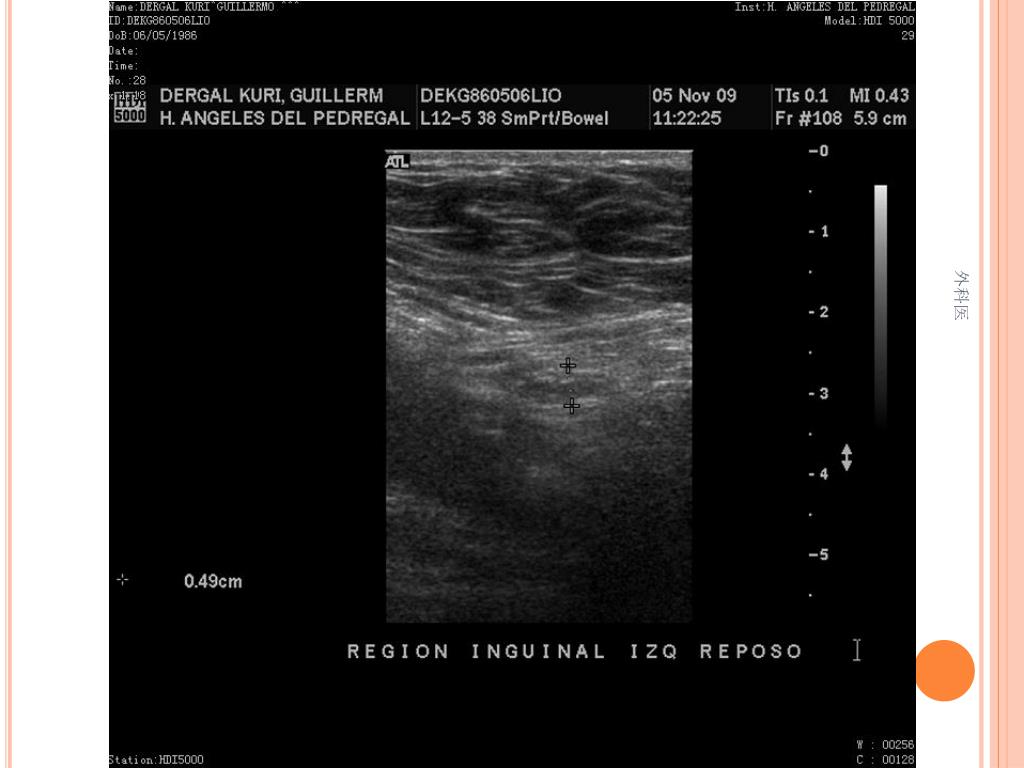

36. PATOLOGIA 外科医

41. PRODUCTO DE RESECCION INTESTINAL: APENDICITIS AGUDA FIBRINOPURULENTA, FIBROSIS PERIAPENDICULAR SEVERA. ILEON TERMINAL Y COLON CON HIPERPLASIA LINFOIDE FOLICULAR Y PERITONITIS AGUDA 外科医